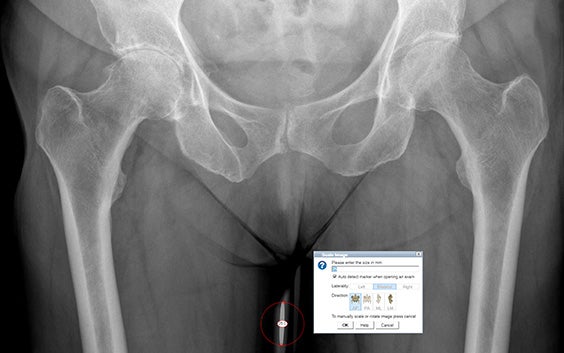

Détection automatique

Mise à l'échelle rapide des radiographies de la hanche sans cliquer sur un marqueur grâce à la détection automatique des marqueurs de mise à l'échelle les plus courants